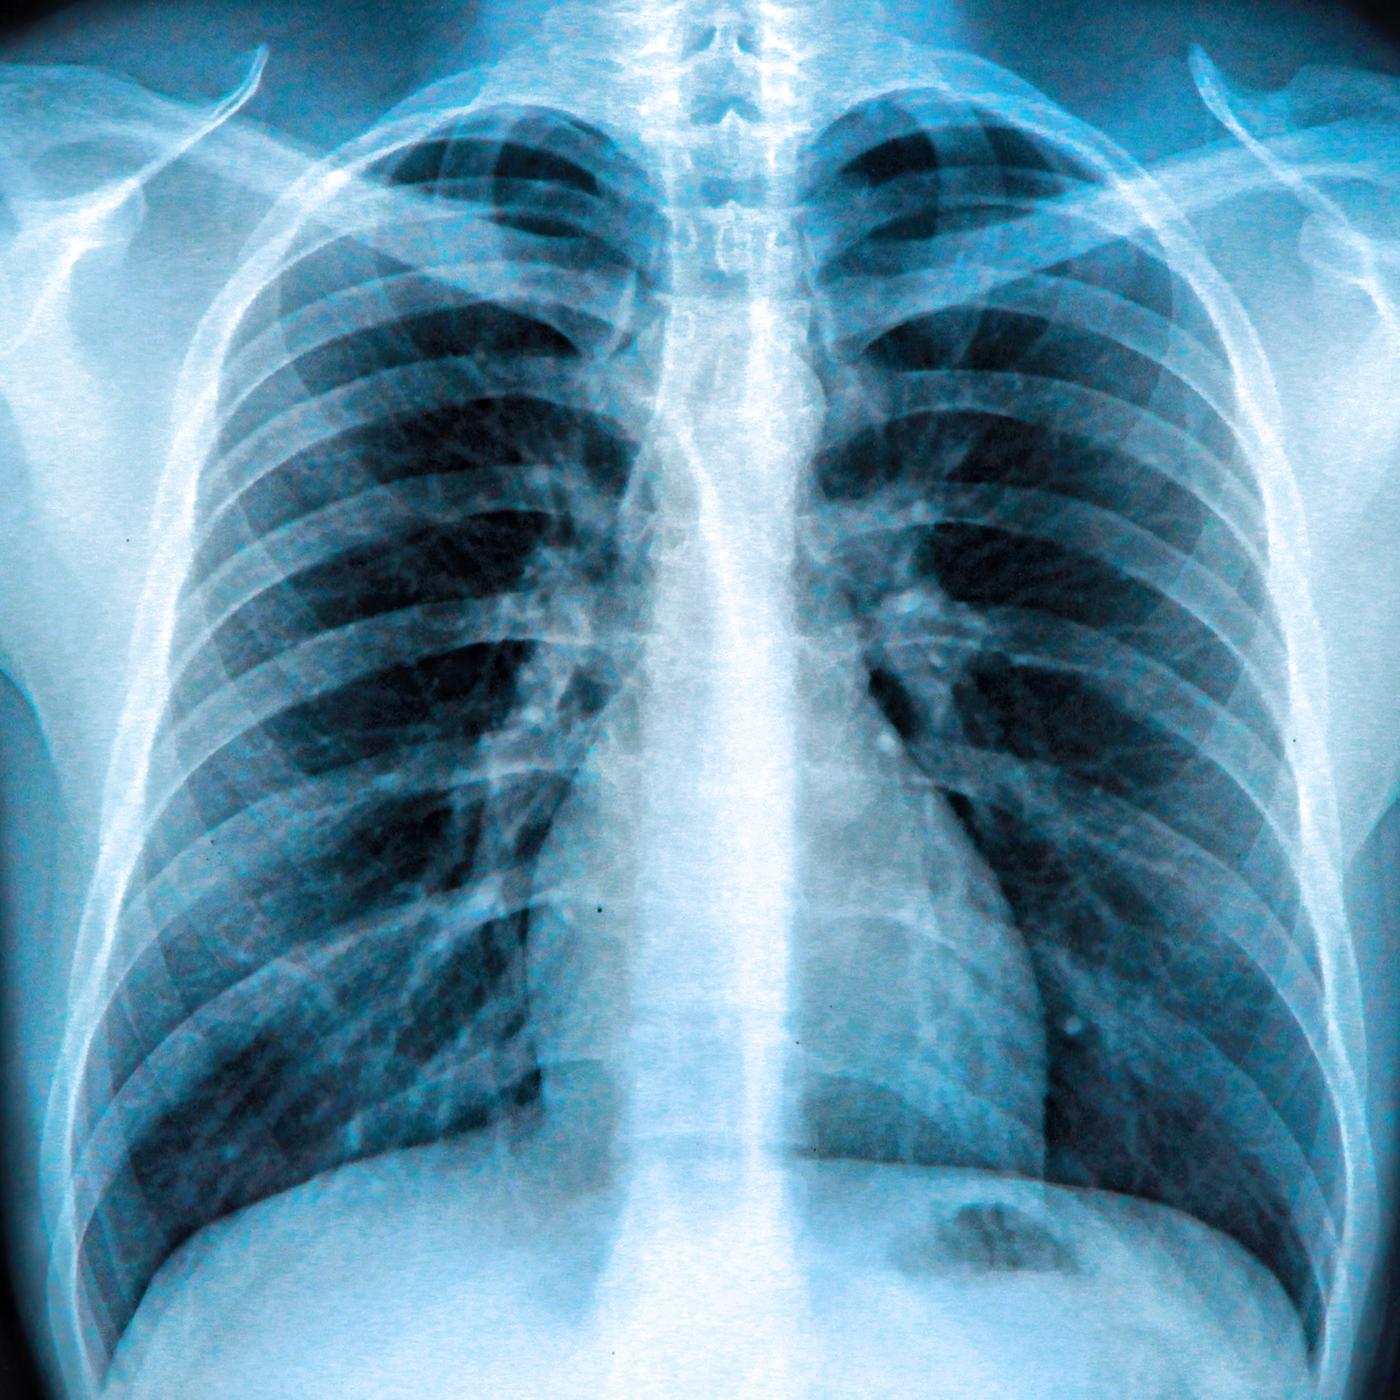

Künstliche Intelligenz wird die Medizin revolutionieren. Algorithmen und neuronale Netzwerke eröffnen ungeahnte Möglichkeiten für Prävention, Früherkennung, Diagnose und Therapie.

Schon heute kann die KI in beliebig vielen Patientendaten Muster erkennen. Sie analysiert in kürzester Zeit Symptome, Therapien und Krankheitsbilder von vielen Patienten und zieht daraus Rückschlüsse auf die richtige Therapie für den Einzelnen.

Auch die Prävention wird vom Einsatz der neuen Technologien massiv profitieren. Sogar zum frühestmöglichen Zeitpunkt, wenn es zum Beispiel darum geht, bestimmte genetische Dispositionen zu erkennen und auszuschalten. Mit der Einführung der elektronischen Patientenakte könnte Deutschland eine Vorreiterrolle in der medizinischen Forschung einnehmen. Heute schon helfen neuronale Netzwerke und Algorithmen bei der Früherkennung verschiedener Krebsarten und bei der Entwicklung einer individuellen Therapie.

Nahezu unbegrenzte Möglichkeiten ergeben sich auch in der Diagnostik. Schon bald könnte es Ärzten weltweit möglich sein, mit Augmented-Reality-Brillen direkt in den menschlichen Körper zu blicken. Ärzte sind mittels KI-Apps in der Lage, Laborergebnisse sehr viel schneller auszuwerten und personalisierte Therapieempfehlungen zu geben. KI gesteuerte Robotik unterstützt Chirurgen bei komplexen Eingriffen, bei denen es um Millimetergenauigkeit geht.